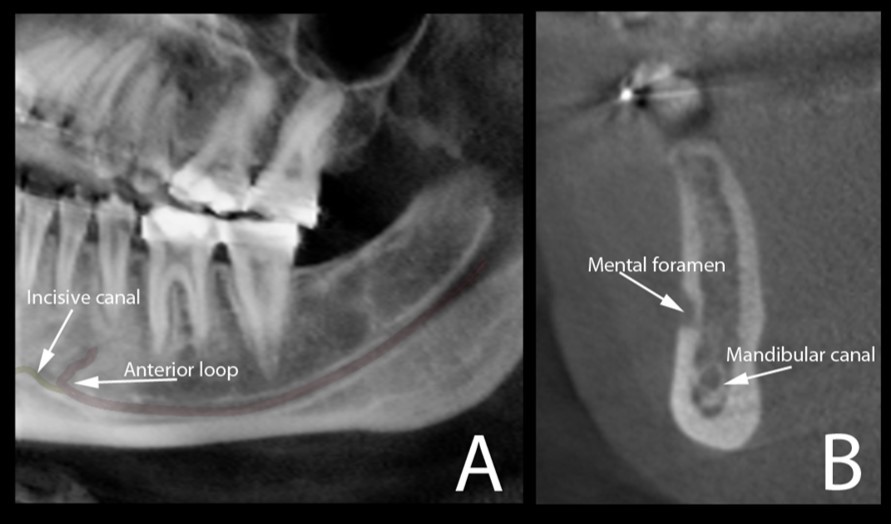

Figure 3.Cone beam CT image (A) shows the oblique reconstruction of the volume of interest at the region of premolars. In this reconstruction, the anterior loop of the mandibular canal can be clearly observed before the start of the incisive canal. The appearance of this anterior loop in a cross-sectional view is shown in image (B).

Cone beam CT image (A) shows the oblique reconstruction of the volume of interest at the region of premolars. In this reconstruction, the anterior loop of the mandibular canal can be clearly observed before the start of the incisive canal. The appearance of this anterior loop in a cross-sectional view is shown in image (B).